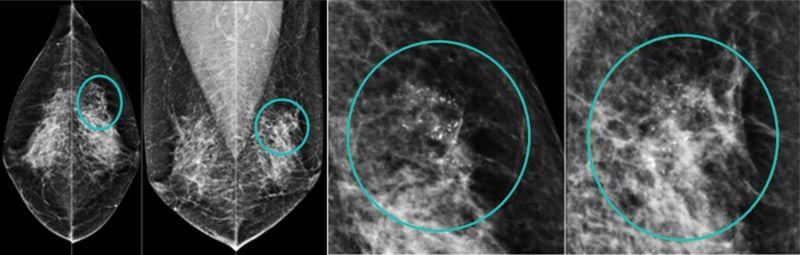

國際公認最有效的篩檢工具,偵測乳房內「微鈣化點、局部組織變形」。台灣研究顯示:每2年接受1次乳房攝影檢查,可降低乳癌死亡率41%、減少30%的第二期以上乳癌發生率。目前國健署補助45至69歲、40至44歲二等親內有乳癌家族史女性「每2年一次免費乳房攝影檢查」,婦女應多加利用。但乳房攝影對亞洲女性高比例的緻密型乳房(高比例乳腺組織),診斷率較差,可合併「乳房超聲波」檢查,以減少檢查盲點,增加診斷率。

乳房X光攝影檢查可偵測乳房內微鈣化點、局部組織變形。

56歲王小姐,在國健署免費乳房攝影篩檢後發現:左乳房外上方有一群聚微鈣化點,經手術證實為乳癌初期,後續恢復良好。